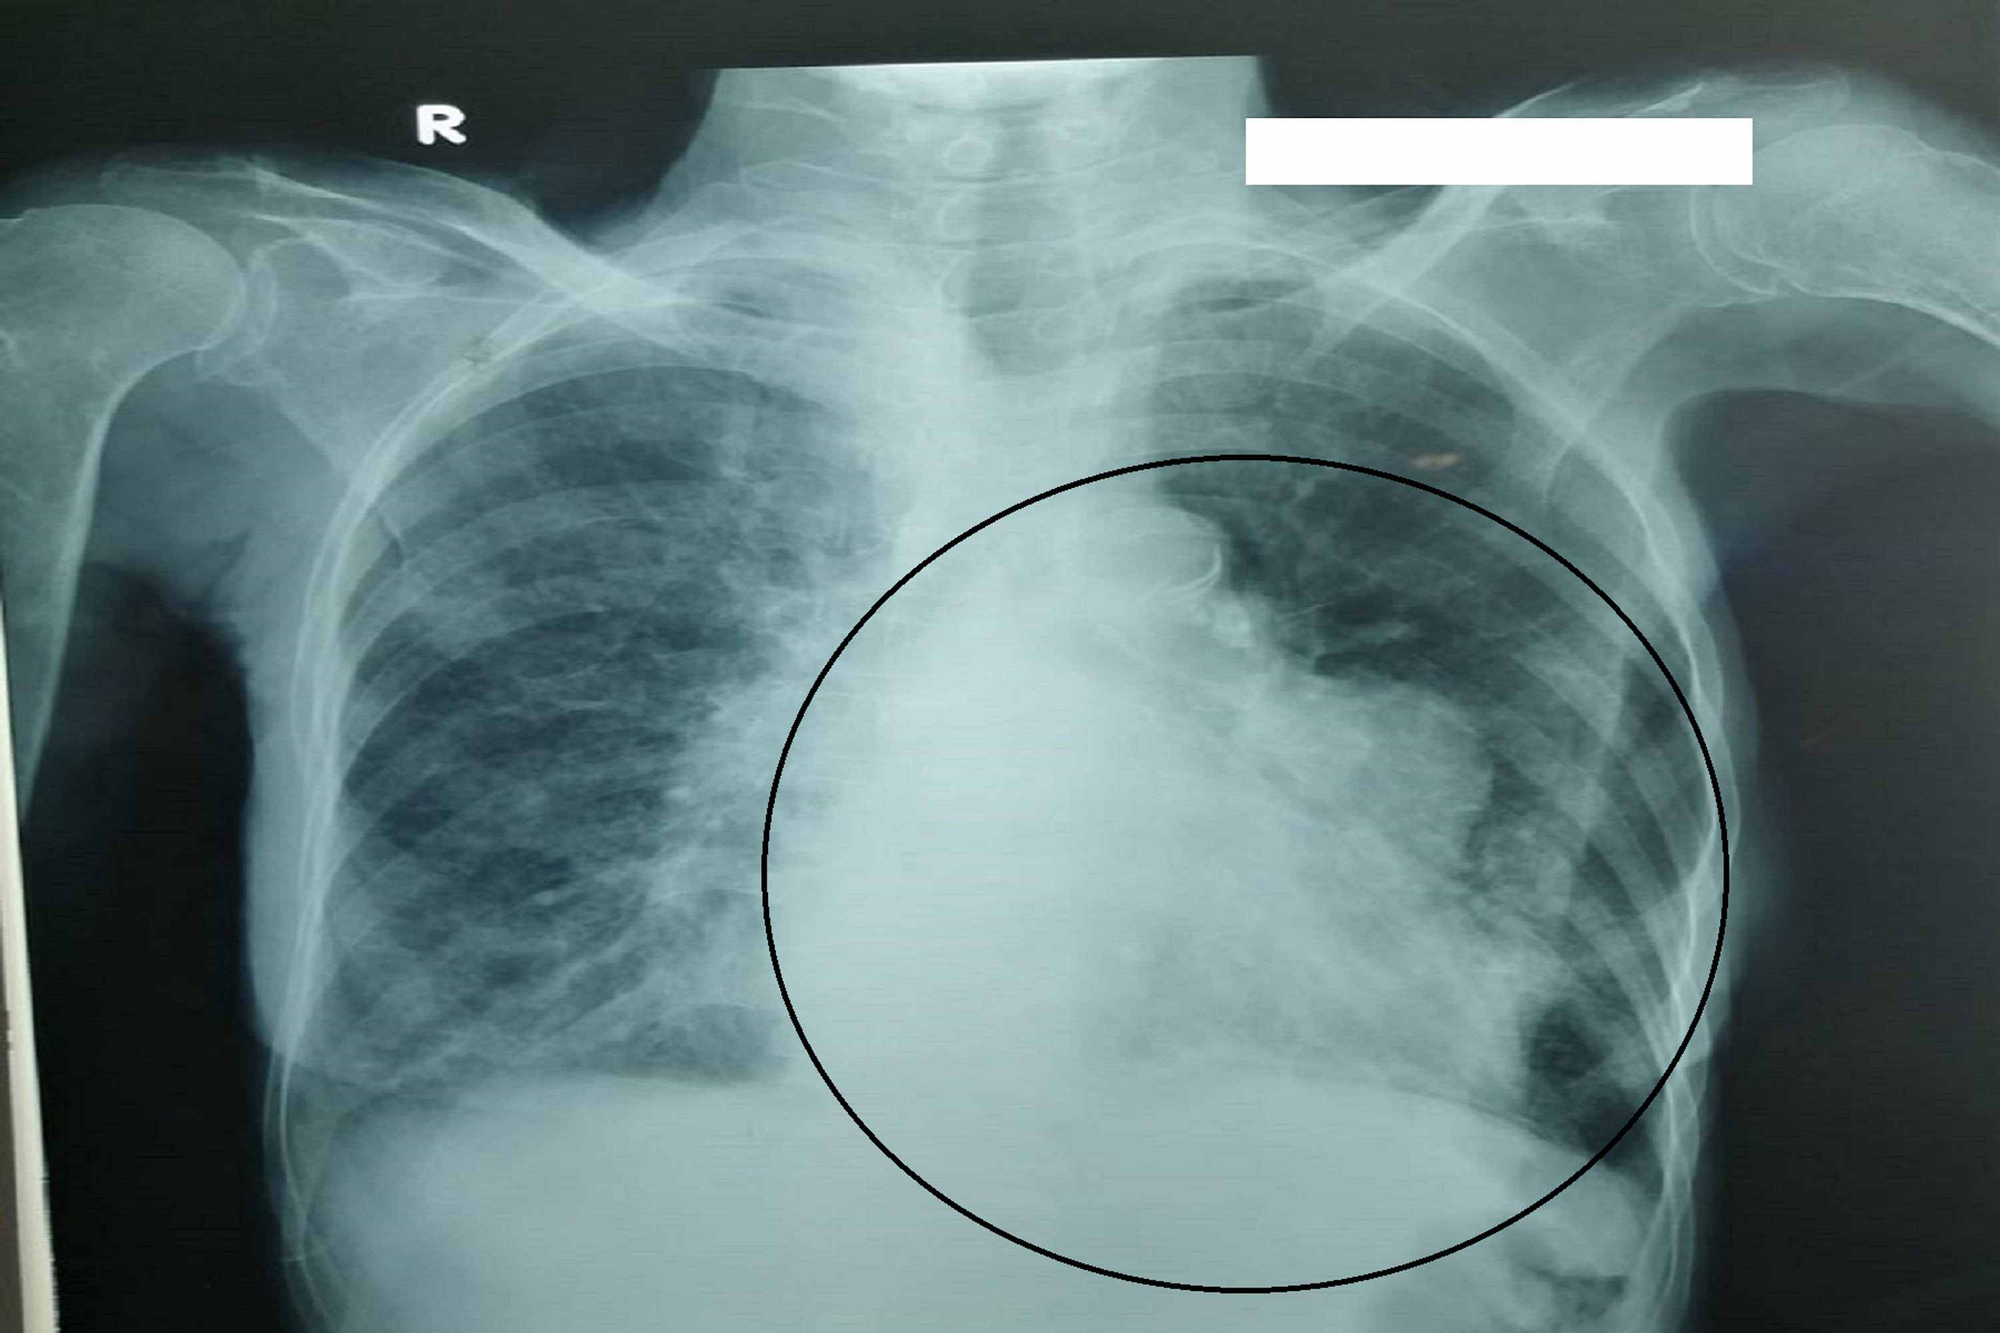

Chest Xray on presentation showing cardiomegaly Download Scientific

Chest Xray on presentation showing cardiomegaly Download Scientific Lupus And Chest X Ray Citation, doi, disclosures and article data. Last revised by arlene campos on 14 jun 2024. Last revised by arlene campos on 14 jun 2024. Learn how lupus can affect the lungs and cause chest pain, shortness of breath, and other complications. Thoracic manifestations of systemic lupus erythematosus. Systemic lupus erythematosus (thoracic manifestations) | radiology reference article | radiopaedia.org. For example,. Lupus And Chest X Ray.